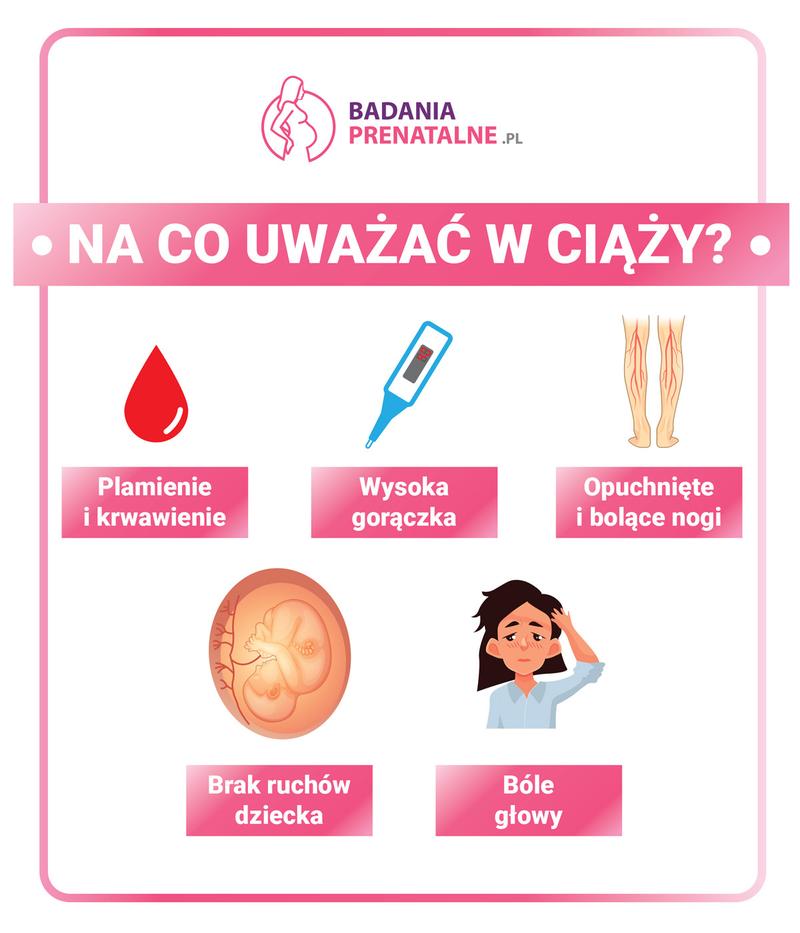

W przeważającej większości przypadków plamienie okazuje się niewielkie i trwa zazwyczaj nie dłużej niż dwa dni. Często towarzyszy mu zmiana koloru wydzieliny, która może przybierać odcienie brązowe lub różowe. Warto jednak zachować czujność w kontekście intensywności plamienia; jeśli krew przybiera świeży kolor, a jej ilość przypomina menstruację, zdecydowanie warto zgłosić się do lekarza. Dodatkowo objawy takie jak ból czy skurcze mogą sugerować, że sytuacja nie jest w porządku i należy udać się na wizytę kontrolną.

Jeśli po badaniu spostrzeżesz intensywne krwawienie, które przypomina miesiączkę lub towarzyszą mu skrzepy, zdecydowanie powinnaś skonsultować się z ginekologiem. Kluczowa różnica między plamieniem a krwawieniem tkwi w ilości wydobywającej się krwi. Plamienie zazwyczaj ma postać lekkiego lub brązowego śluzu, natomiast krwawienie cechuje się znacznie większą obfitością i wymaga stosowania podpasek. Oprócz intensywności krwawienia, zwróć również uwagę na dodatkowe objawy, takie jak ból w podbrzuszu lub skurcze. W takim przypadku warto natychmiast udać się na izbę przyjęć, aby upewnić się, że wszystko jest w porządku.

Plamienie po badaniu ginekologicznym, zwłaszcza w czasie ciąży, może naturalnie budzić niepokój. Jako przyszła mama rozumiem te obawy; jednak warto wiedzieć, że w wielu przypadkach to zjawisko mieści się w zakresie normy i nie oznacza żadnej patologii. Jeśli doświadczysz lekkiego plamienia po wykonaniu cytologii, musisz mieć świadomość, że to efekt podrażnienia tkanki szyjki macicy. Jak już poruszamy ten temat, przeczytaj nasz poradnik o radzeniu sobie z pękniętą szyjką macicy po porodzie. Warto pamiętać o zasadzie: im więcej krwi, tym większe zmartwienie, dlatego dobrze jest umieć odróżnić plamienie od krwawienia. Plamienie zazwyczaj charakteryzuje się niewielką ilością krwi, której odcienie mogą być różowe, brązowe lub śluzowe, podczas gdy krwawienie to intensywny wyciek świeżej krwi, mogący wymagać interwencji medycznej. Jeśli masz chwilę, sprawdź, jak długo trwa krwawienie po porodzie i co warto wiedzieć.

Warto w tym miejscu podkreślić, jak istotne jest odróżnienie plamienia od intensywnego krwawienia. Plamienie zazwyczaj objawia się niewielką ilością krwi, często w postaci brązowej lub różowej wydzieliny, która nie przechodzi przez bieliznę. Natomiast krwawienie, które może wywoływać poważniejsze zmartwienie, pojawia się wtedy, gdy występuje intensywna, świeża krew oraz może zwiastować problem wymagający pilnej interwencji medycznej. W sytuacji, gdy plamienie po cytologii trwa dłużej niż dwa dni lub towarzyszą mu inne niepokojące objawy, takie jak ból czy silne skurcze, warto jak najszybciej skonsultować się z lekarzem.

Objawy, które mogą sugerować większe problemy po cytologii, to:

- Intensywne krwawienie, które wymaga zmiany podpaski co godzinę lub częściej

- Silny ból w podbrzuszu, który nie ustępuje

- Obecność skrzepów krwi w wydzielinie

- Obrzęk lub zaczerwienienie w okolicy szyjki macicy